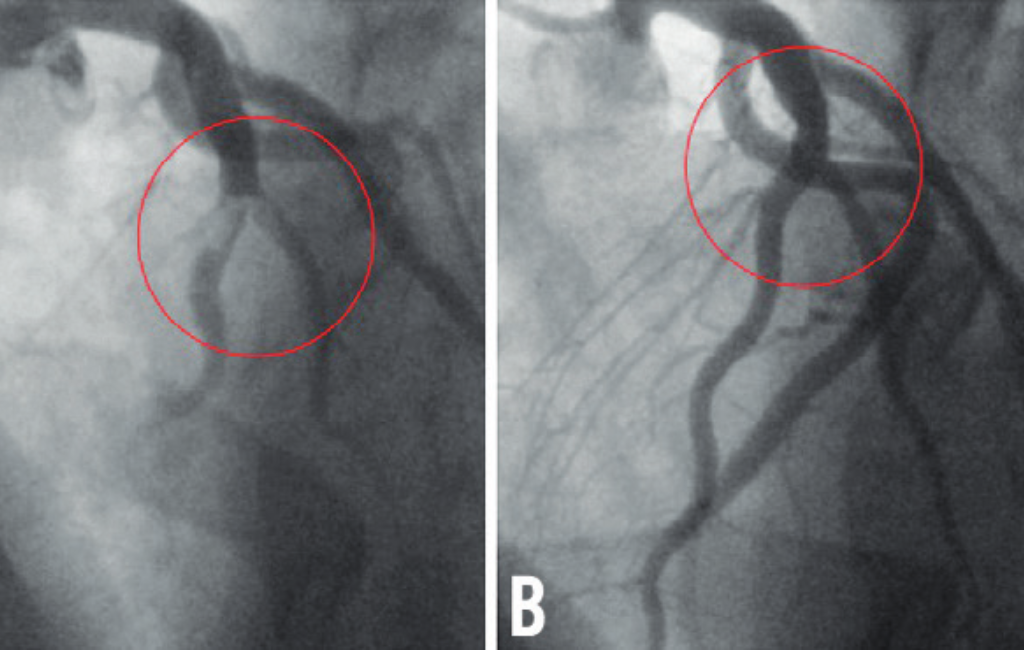

Angioplasty & Stent Placement – Restoring Blood Flow to the Heart

• Balloon Angioplasty & Stenting – Non-surgical, quick recovery treatment for heart blockages.

• Drug-Eluting & Bioabsorbable Stents – Advanced solutions for artery widening.